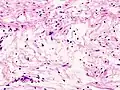

- Antoni A area of schwannoma with Verocay bodies (one annotated by circle)